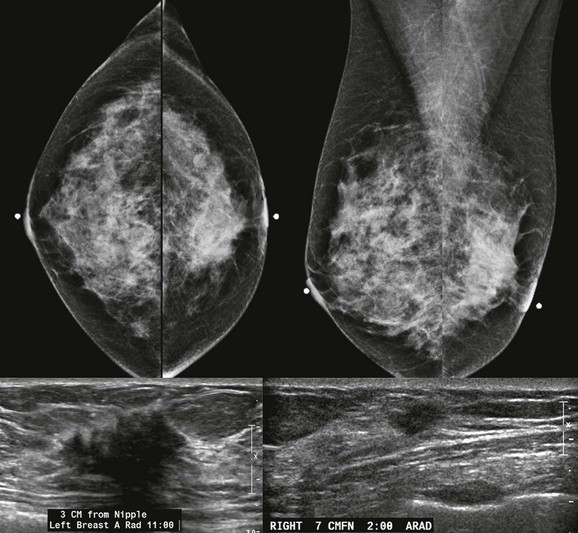

When the tumor is very large, the breast affected with ILC can appear to be getting smaller on mammography—the “shrinking breast” (Fig. 11-3). This is not due to the breast becoming physically smaller, but to the decreased compressibility of the breast tissue that is full of webs of cancer cells. If the contralateral breast compresses to a thickness of 5 cm, a breast with extensive ILC may only compress to 8 cm. Although this results in the appearance of a smaller breast on mammography, breast size is typically symmetric on clinical examination.

FIGURE 11-3 Shrinking Breast.

A 52-year-old woman noted thickening in her left breast. On clinical examination, the breasts are symmetric in size but the texture of the left breast is diffusely thickened. On mammography, the left breast appears to be smaller than the right. Biopsy showed ILC. Did you also notice the one-view asymmetry in the right medial breast? US of this area shows a small hypoechoic mass. Biopsy of the right breast showed IDC.

On US, ILC may present as a defined mass (see Fig. 11-3) but more often presents as ill-defined areas of shadowing without a distinct mass (see Fig. 11-2). The lines and arcs of tumor can produce bands of shadowing, like the edges of a spider web. Although tumor size is often underestimated by US, this modality is more accurate than clinical examination or mammography in assessing extent of disease.